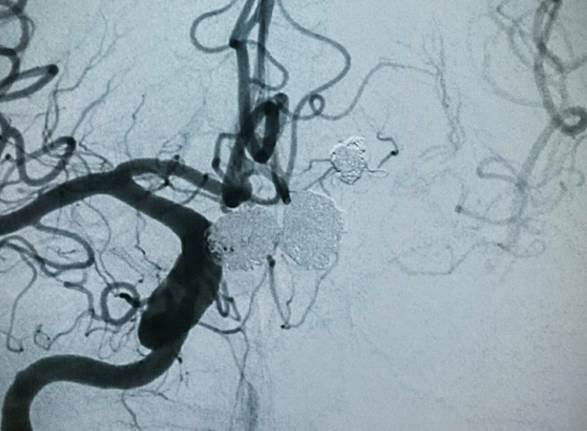

Controle final pós embolização